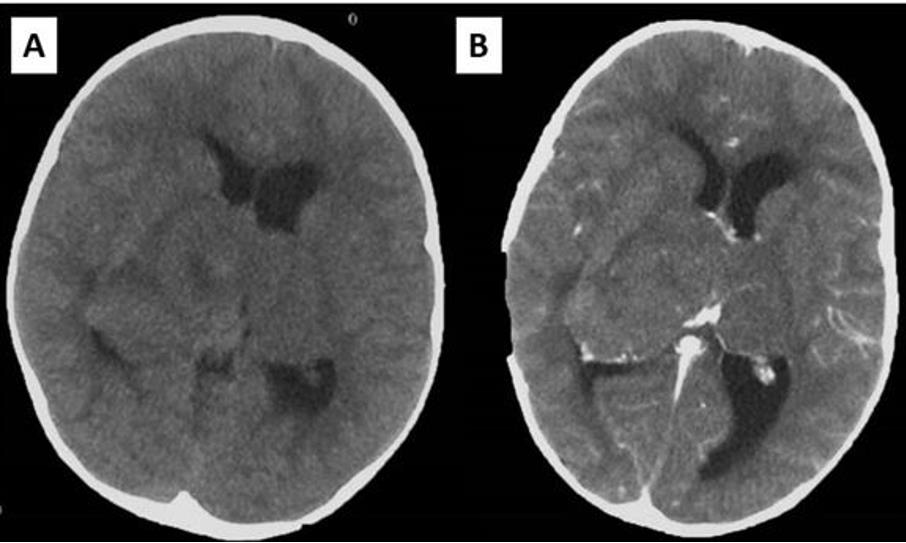

Postoperative MRI showed residual tumor in the left thalamic region, and radiotherapy was performed, followed by chemotherapy. Residual tumor regression was confirmed with MRI, and the patient was stable almost for 2 years. She was monitored with MRI every 3 months (Figure 3). However, twenty-one months after surgery and two months after previous brain MRI which showed no signs of tumor regrowth, child was referred to our department with acute consciousness deterioration, drowsy, adynamic with Glasgow coma score of 10 points. Brain CT showed bleeding in the region of the corpus callosum, and MRI, confirmed bleeding within the genum of corpus callosum and symmetrical extension into the white matter of both frontal lobes. On the post contrast tomograms tumor component could not be identified (Figure 4). The patient had low platelet number, so impaired coagulation was suspected as the cause of bleeding. MSCT angiography was normal. Hematoma was evacuated and biopsy samples were taken. The child recovered well after operation. Pathohistological examination revealed that the cause of bleeding was high grade glial tumor. This time the definite diagnosis was Glioblastoma.

Figure 4: Imaging studies demonstrating hemorrhage: (A) Brain CT showing hemorrhage in the region of corpus callosum; (B) Brain MRI showing signs of bleeding within the corpus callosum and extension into the white matter of both frontal lobes presented in postcontrast T1W; (C) sagittal T1W sequence, (D) T2W sequence.